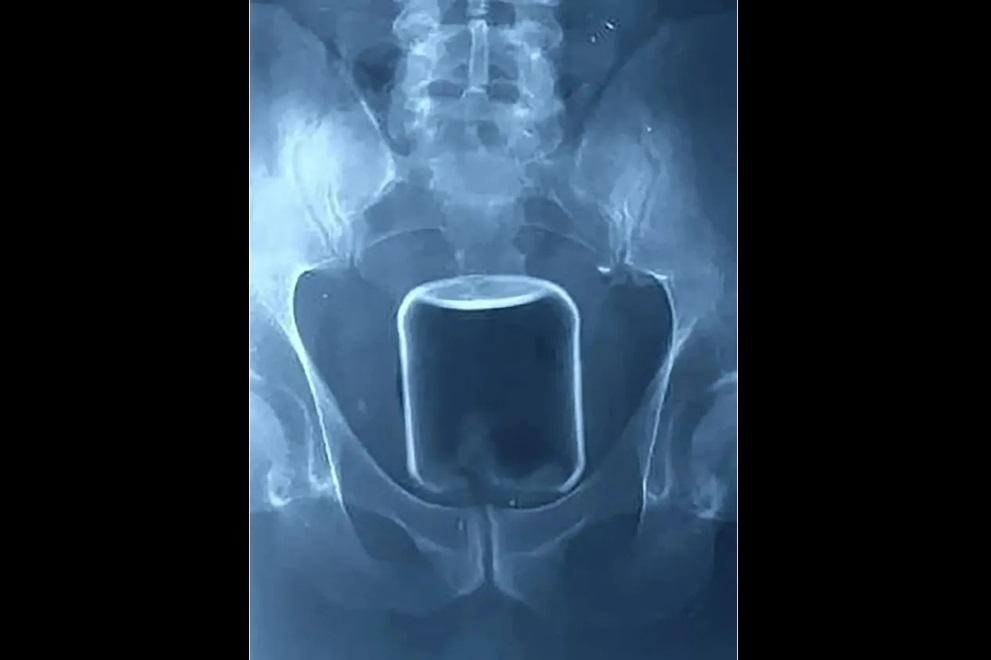

俄羅斯一名男子將500毫升的玻璃瓶塞進肛門。(互聯網)

從報道顯示的X光片看見,體積不細的玻璃瓶在肛門內較高位置,醫生最後成功取出它,連帶一個安全套。報道稱,那男子將一個容量500毫升的玻璃瓶塞進肛門,並將其推進腸道,最後因無法取出而求醫。俄羅斯下諾夫哥羅德一間醫院公開有關個案,稱醫生非道德警察,不會評論病人非傳統的性傾向,呼籲民眾若遇相同情況,須尋求醫療協助。